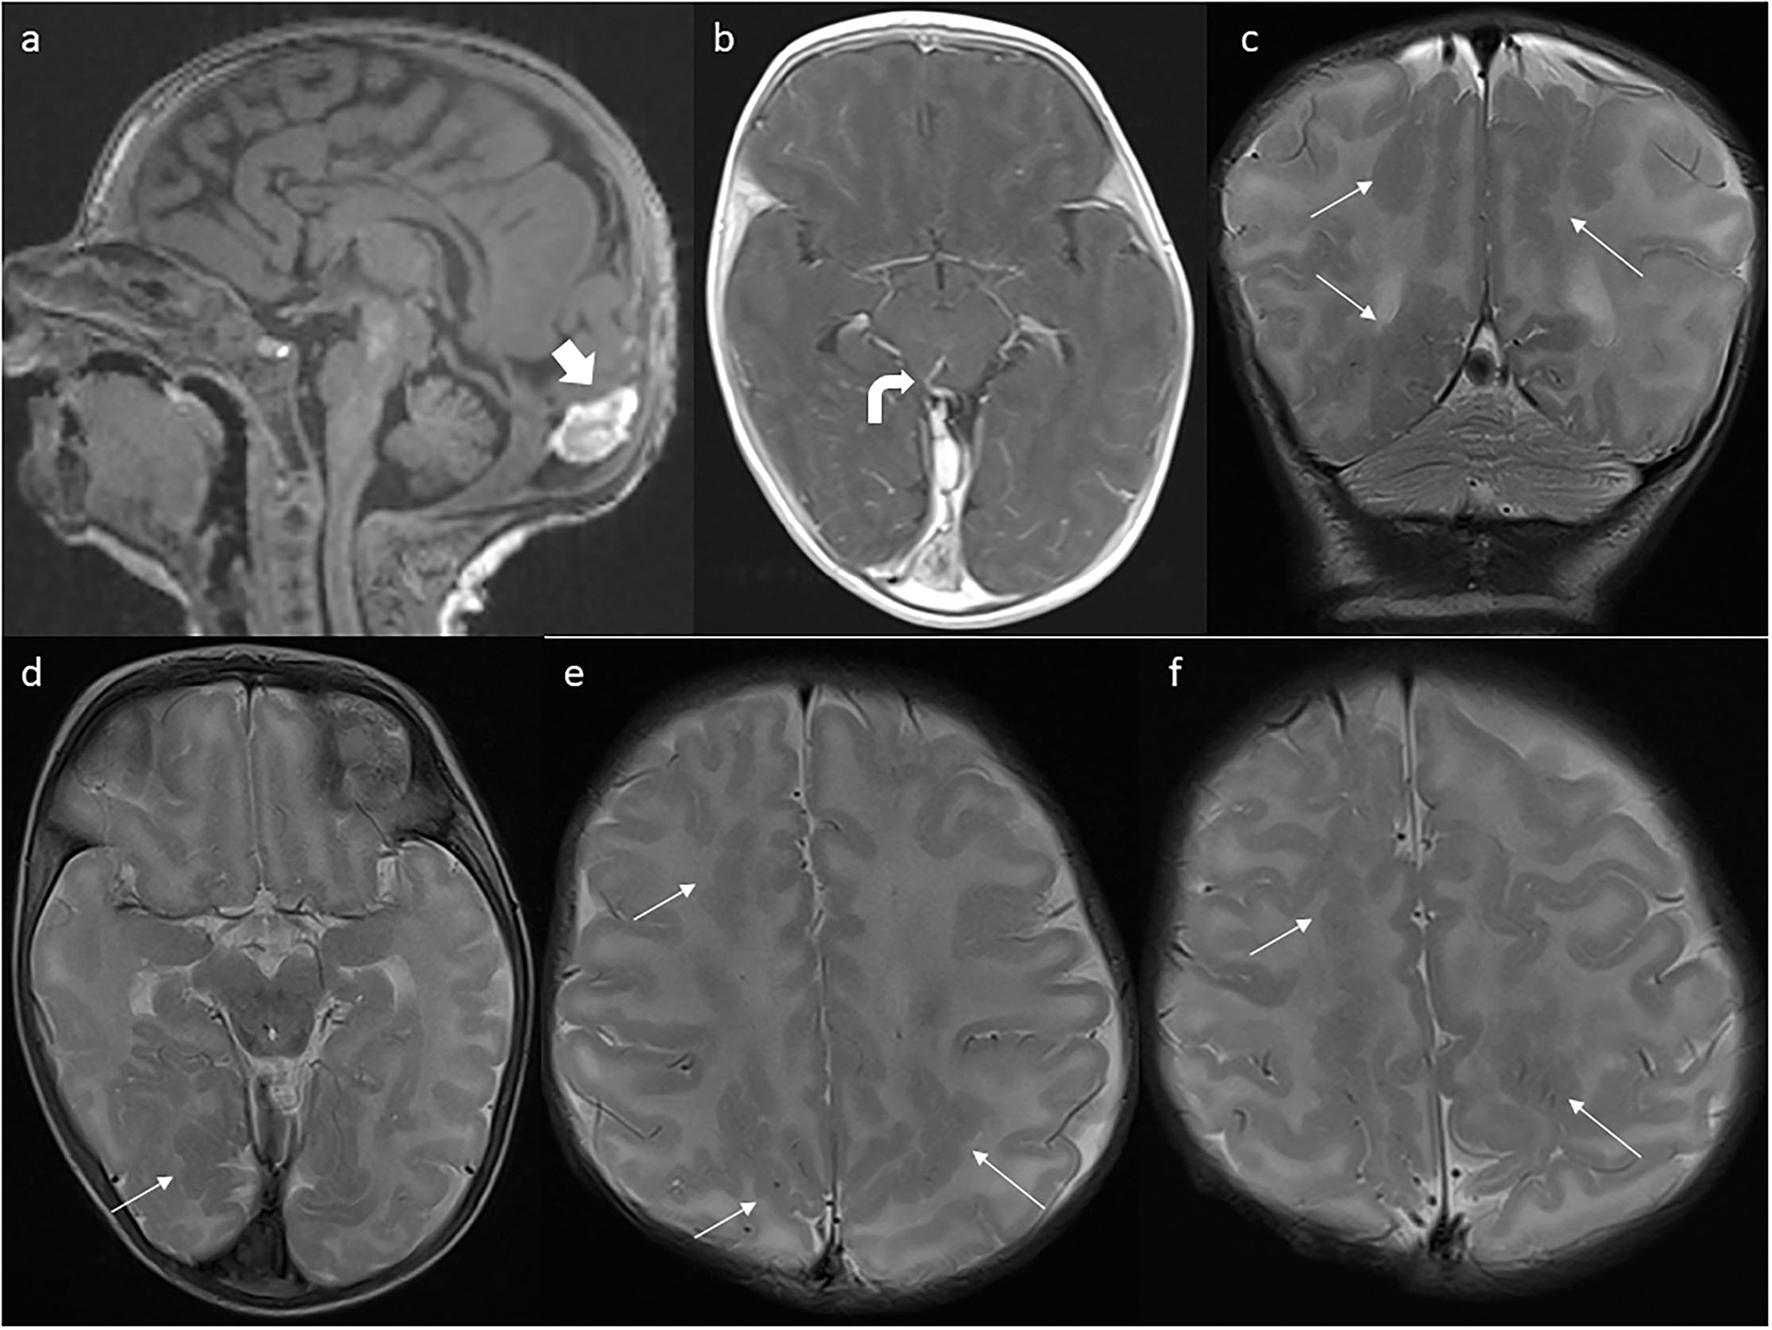

Figure 3

First postnatal MRI scan at the age of 4 weeks. (a) Partial regression of dural ectasia (thick arrow). (b) One of the abnormal vessels (curved arrow). (c) Bilateral parasagittal polymicrogyria (thin arrows) in coronal and (d–f) axial planes.

In the 4th week of the girl's life, the brain MRI revealed a torcular pseudomass (20 × 8 × 12 mm) (Figures 3a,b) and deposits of hemosiderin in susceptibility-weighted imaging (SWI) sequence. The most striking finding was diffuse bilateral parasagittal occipital, parietal, and frontal polymicrogyria (Figures 3c–f). Abnormal vessels—probably venous anastomoses—were shown in the dorsal part of the midbrain (Figure 3c) and in the lower part of the left cerebellar hemisphere. On physical examination, hypertonia, tendency to scapular retraction, and epistotonus while in prone position were diagnosed. The patient was referred to the neurologic and neurosurgical outpatient clinics as well as to intensive rehabilitation.